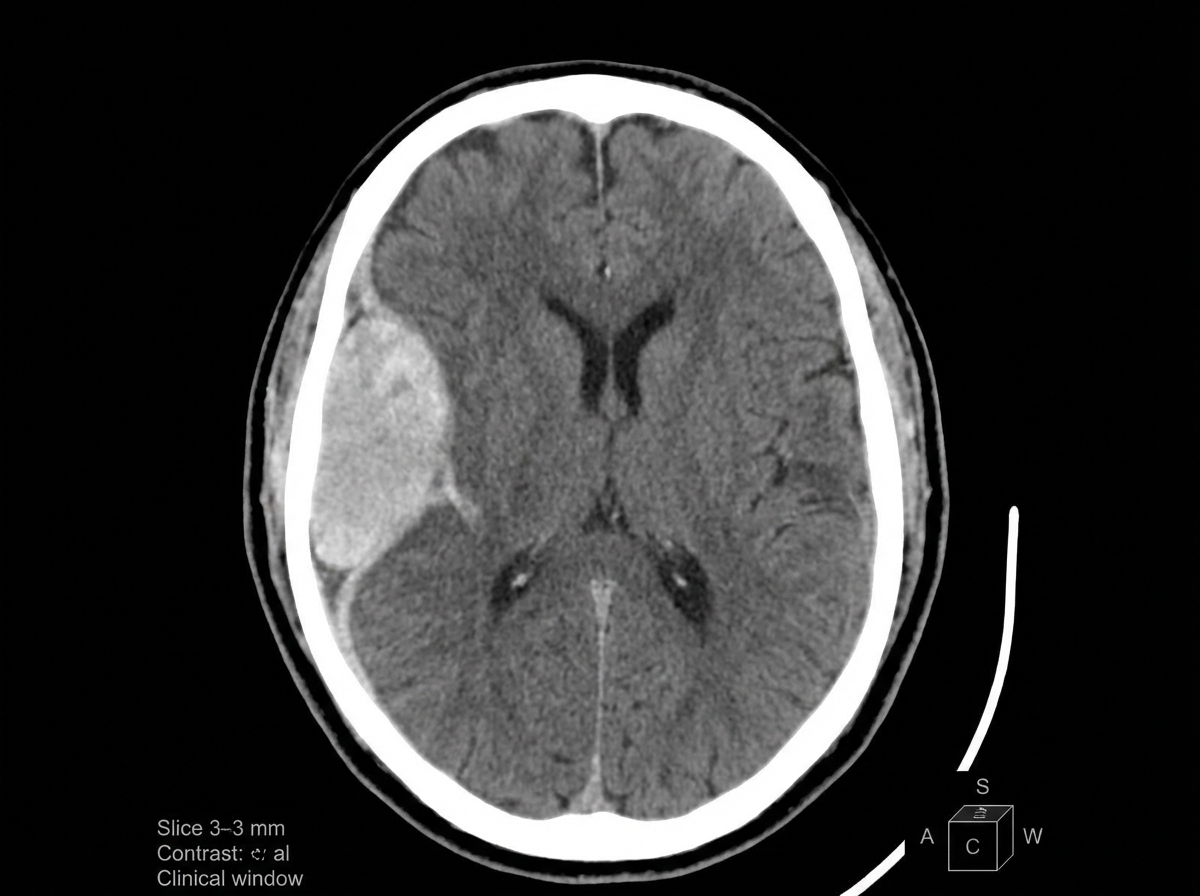

A 41-year-old woman presents to the office with a complaint of a headache for 1 month and an episode of abnormal body movement. The headaches are more severe in the morning, mostly after waking up. She doesn’t give a history of any major illness or trauma in the past. Her vital signs include: blood pressure 160/80 mm Hg, pulse 58/min, temperature 36.5°C (97.8°F), and respiratory rate 11/min. On fundoscopic examination, mild papilledema is present. Her pupils are equal and reactive to light. No focal neurological deficit can be elicited. A contrast computed tomography scan of the head is shown in the picture. Which of the following is the most likely biopsy finding in this case?